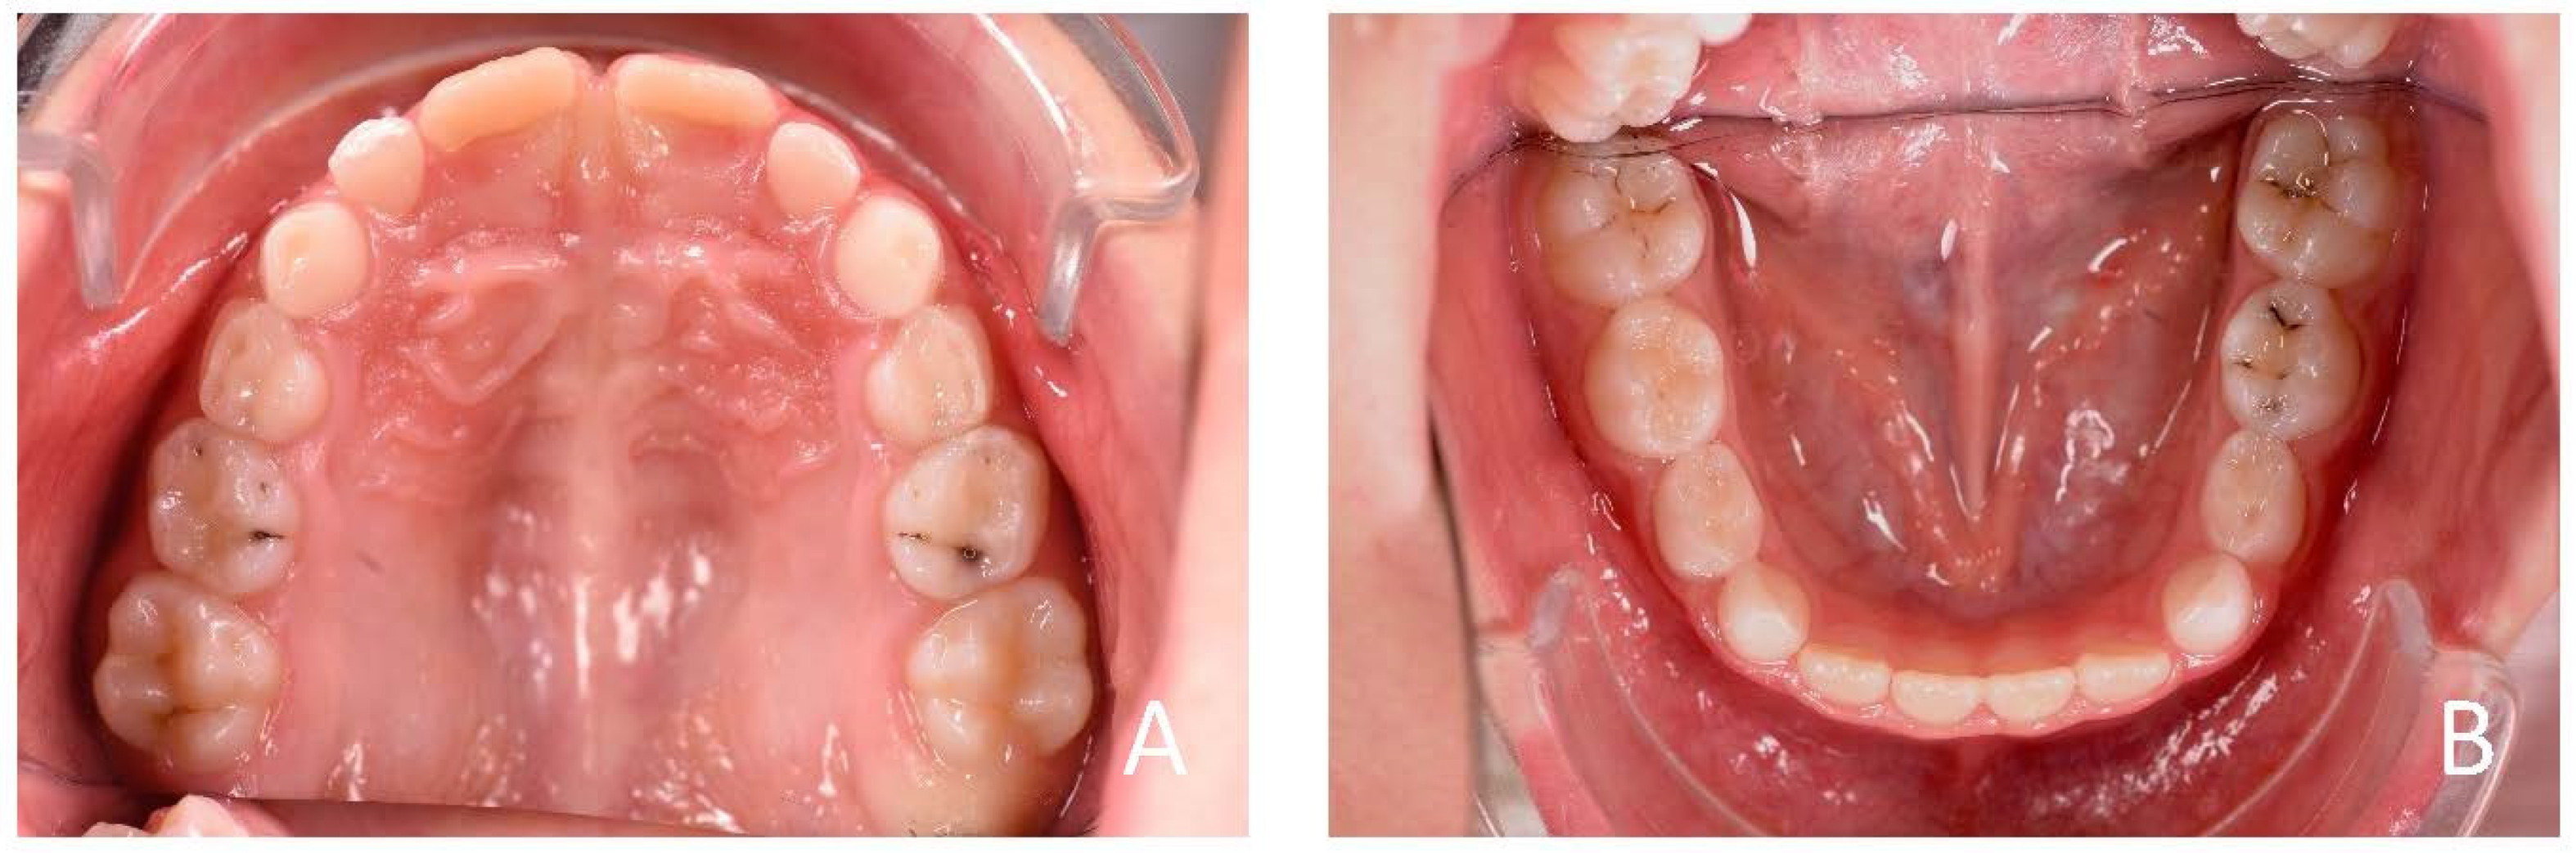

3.1. Clinical Case #1

3.2. Clinical Case #2

3.3. Clinical Case #3

3.4. Clinical Case #4